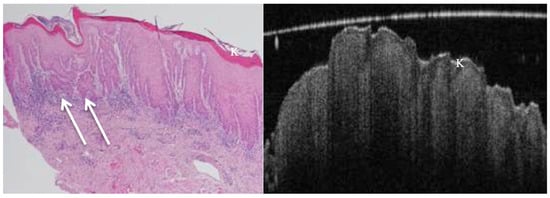

OCT performed well in discriminating dysplasia grades (Figure 1, Figure 2, Figure 3 and Figure 4). The AUC was 0.89 with an 88.0% sensitivity and 90.0% specificity for mild dysplasia. For moderate dysplasia, the highest accuracy was found: 85.0% sensitivity and 92.0% specificity yielded an AUC of 0.91. Severe dysplasia and CIS presented with lower values: the AUCs were 0.87 and 0.86, respectively (Table 4).

Figure 3. OCT (in vivo) and histopathology images reveal hyperkeratosis and severe epithelial dysplasia of a speckled leucoplakia on floor of mouth. Early invasive carcinoma (arrows) shown in the histology image cannot be visualised on the corresponding OCT image due to lack of sufficient depth of penetration as well as the inferior image resolution compared to the H&E-stained section. K = keratosis.